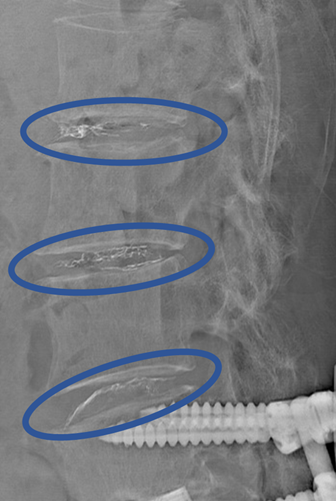

患者様と相談の元、 L1/2、2/3、3/4 にセルゲル法を施行

DiscoGelを入れた後の画像になります。

治療は 40分程度で終了

回復室で休憩後、歩いて帰院されました。